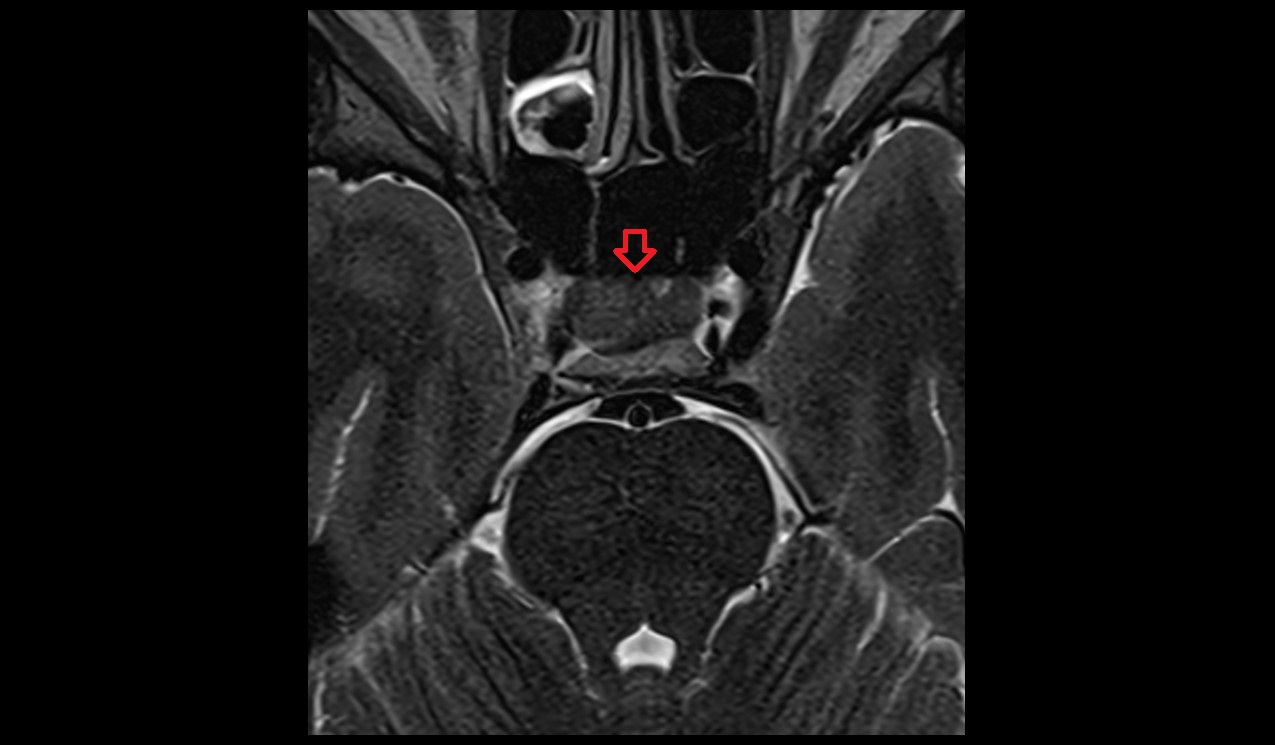

- Peripheral zone of prostate

- Anterior Fibromuscular Stroma of prostate

- Central zone of prostate

- Transitional zone of prostate